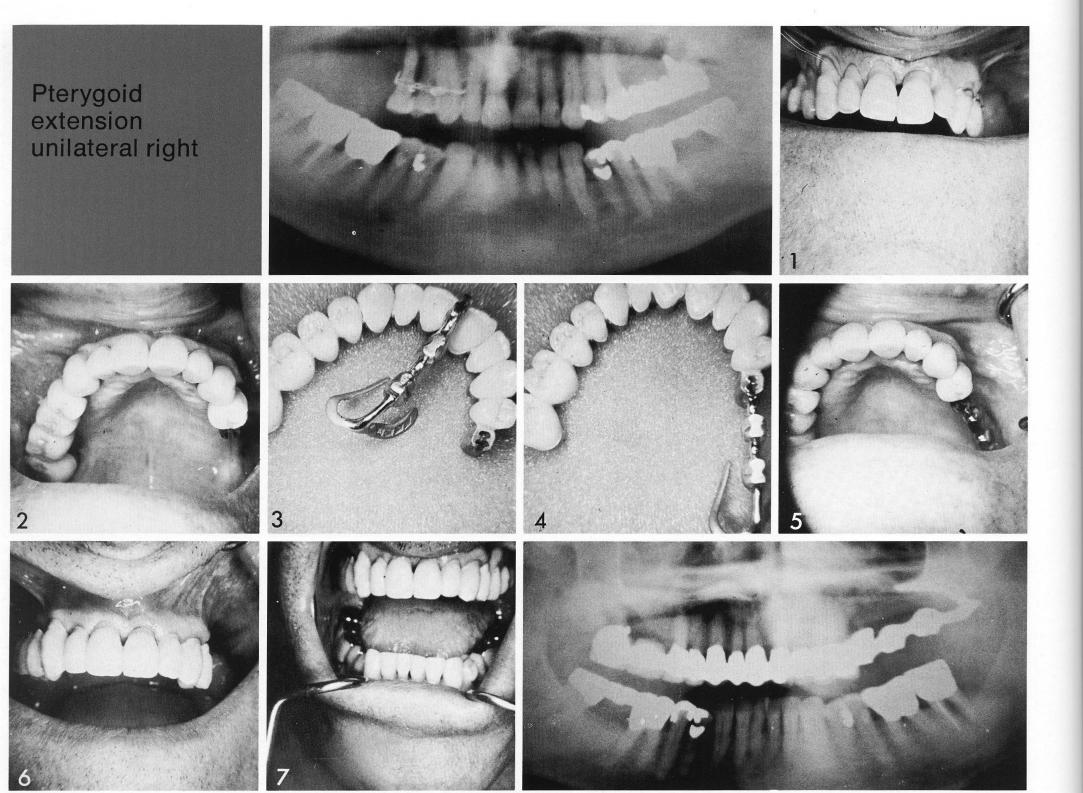

Pterygoid extension

unilateral right

Use of the unilateral pterygoid extension implant has been very satisfying. This is one of the older cases. The patient's remaining teeth were unattractive (I), so they were restored first (2). The site was revealed, and an impression taken of the bone. The entire bridge with its distal pontic and the bone impression were then picked up with a full plaster impression. The resulting unilateral pterygoid extension implant was designed to link anteriorly with the female attachment (3,4). The restoration was refitted, and the implant inserted. After the tissues over the pterygoid extension implant healed (5), an impression was taken for the final three-unit splint that would complete the restoration (7). The age of this pterygoid extension implant can be deduced from its design. Early designs, such as this, had narrow palatal and buccal arms embracing the tuberosity, and a bar arising directly from the hamular notch.

1 Impression for maxillary three unit splint to complete the restoration